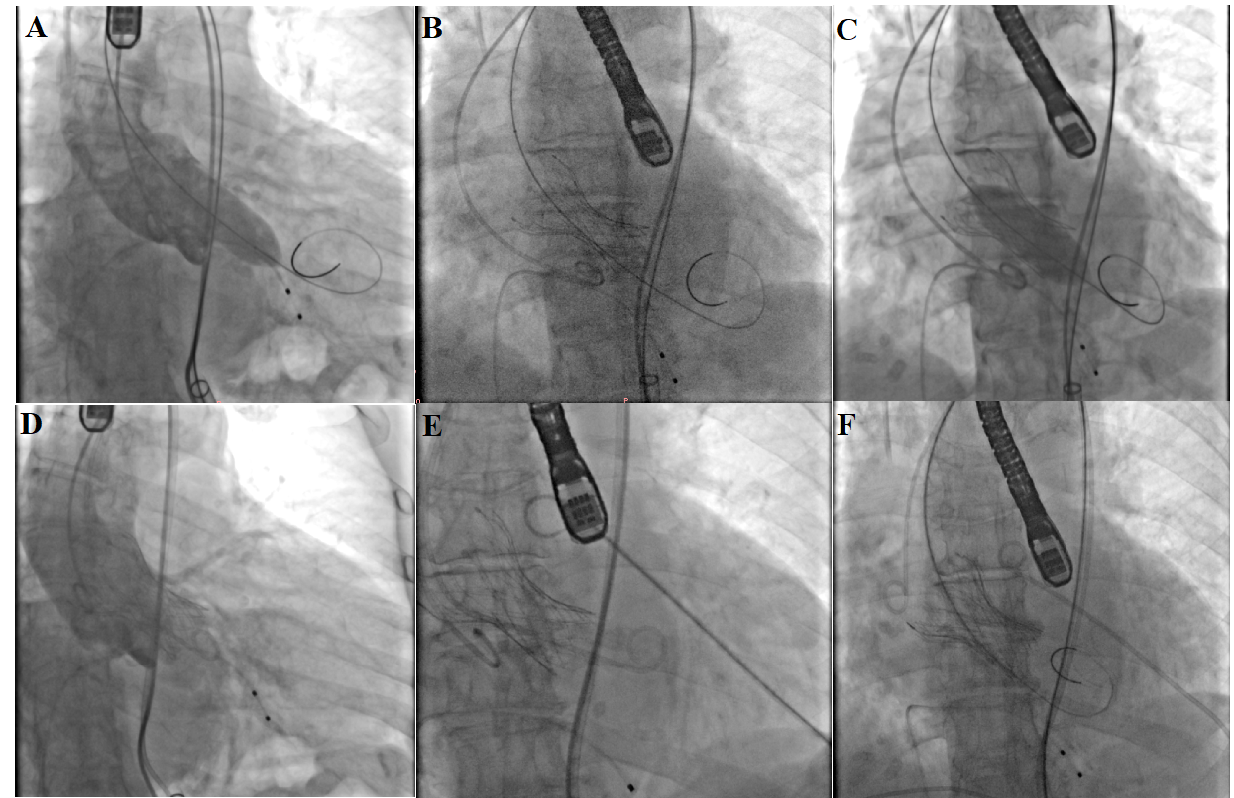

An 85-year-old woman was admitted to our hospital with severe symptomatic aortic stenosis. Preoperative computed tomography and transesophageal echocardiography (TEE) revealed a type I bicuspid aortic valve (aortic annulus diameter: 26 mm; Figure 1, Videos 1 and 2). After pre-dilation with an 18-mm balloon (Figure 2A, Video 3), a 26-mm self-expandable Taurus valve (PEIJIA Medical) was deployed (Figure 2B, Video 4). After valve expansion, post-dilation was performed using the 18-mm balloon (Figure 2C, Video 5). Aortography post-dilation indicated middle paravalvular leakage (Figure 2D, Videos 6 and 7), and the patient’s hemodynamics became unstable. TEE revealed cardiac tamponade and tissue swelling around the left sinus, with extensive calcification bulging out during post-dilation (Figure 3, Videos 8 and 9). Despite pericardial fluid drainage, autologous blood transfusion, and antagonizing anticoagulation (Figure 2E), the pericardial fluid increased in volume. After a second 26-mm valve was implanted within the first prosthesis (Figure 2F, Video 10), the patient’s hemodynamics stabilized. TEE revealed no increase in pericardial effusion and a decrease in the paravalvular leak (Video 11). Thus, valve-in-valve implantation may be an effective treatment to seal post-dilation-induced annular rupture during TAVR.